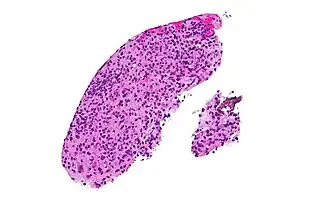

High magnification micrograph of toxoplasmosis

Brain biopsy-High magnification micrograph of toxoplasmosis

Immunohistochemistry displaying positive Toxoplasma gondii trophozoites in a brain biopsy of a HIV immunocompromised individual

Real-time PCR is useful in pathogen detection, gene expression and regulation, and allelic discrimination. This PCR technique utilizes the 5' nuclease activity of Taq DNA polymerase to cleave a nonextendible, fluorescence-labeled hybridization probe during the extension phase of PCR.[63] A second fluorescent dye, e.g., 6-carboxy-tetramethyl-rhodamine, quenches the fluorescence of the intact probe.[63] The nuclease cleavage of the hybridization probe during the PCR releases the effect of quenching resulting in an increase of fluorescence proportional to the amount of PCR product, which can be monitored by a sequence detector.[63] Lymph nodes affected by Toxoplasma have characteristic changes, including poorly demarcated reactive germinal centers, and scattered epithelioid histiocytes.[64]